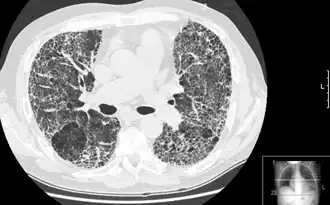

![]() Пневмофиброз как исход интерстициального заболевания лёгочной ткани - «сотовое лёгкое». | |

Большинство интерстициальных заболеваний лёгких приводят к пневмофиброзу. В настоящее время термин «пневмофиброз» не является синонимом ИЗЛ, однако всё ещё употребляется в этом значении. Для обозначения фиброзирующих ИЗЛ с невыясненной первопричиной используется словосочетание «идиопатический пневмофиброз».